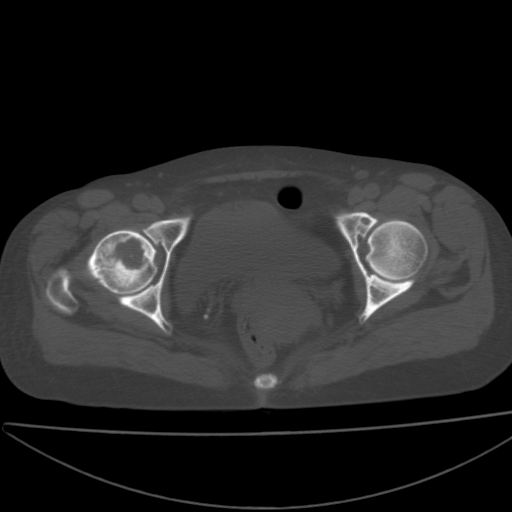

以下是引用xiaoniu在2008-9-6 8:22:00的发言:[br]右侧股骨颈囊性低密度,囊壁边缘硬化,中年妇女,首先考虑:骨囊肿。其次考虑动脉瘤样骨囊肿。[br][br][br][本贴已被 xiaoniu 于 2008-9-6 9:04:54 修改过]